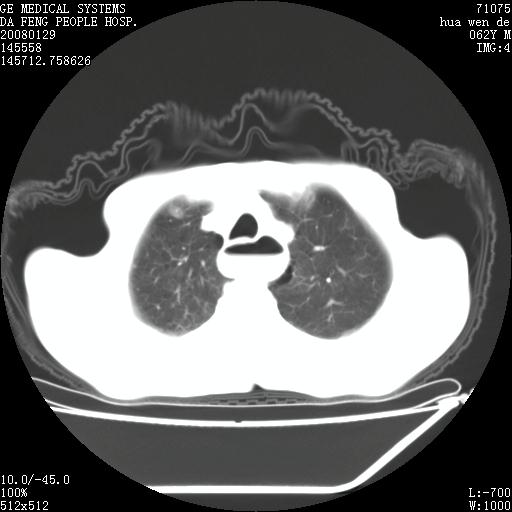

男性,67岁。作肺部检查时发现

1.整个食管扩张,未见明显占位性病变,贲门区亦未见明显占位病变,考虑:贲门失驰缓症;

2.右上肺病变边缘可见毛刺,囊壁厚度不均匀,周围境界较清楚,未见炎性渗出性影,右上肺外带可见片状影,边缘不清,考虑:肺癌伴空洞形成、右上肺炎。

15楼主分析有道理,胸腔胃除外,那么考虑贲门失驰缓症并肺部化脓感染(吸入性)可能。

肺内病灶位于右肺中叶,食道扩张后导致咽部功能受影响,吸入气管可能是存在的。

可疑之处在于:左肺未见吸入性病灶存在。另右肺癌(右肺中央型并阻塞性肺炎)不能除外

食管全程扩张,壁均匀不厚,喷门失弛缓症

右上肺空洞可见液平,临近肺野磨玻璃密度,考虑1.结核2.脓肿

贲门失驰缓症.肺部感染伴脓肿形成。支持!是否吸入性要结合临床诊断,我们影像是看不出来的。但胸腔胃能排除(1.没有手术史支持,2.双侧胸廓对称,胸壁、肋骨及胸膜规整,3,食管壁明显扩张内壁光滑,胸腔胃黏膜皱襞多较厚)。